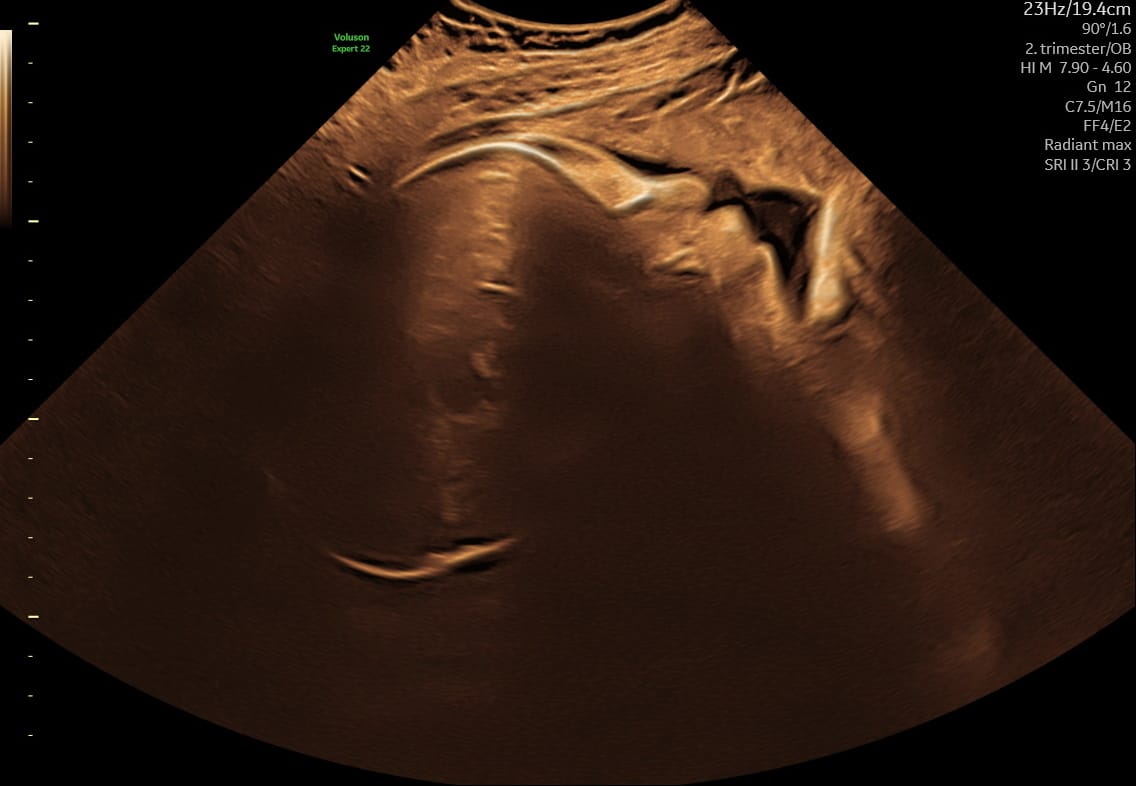

Andet trimester (uge 14–27)

Kønsscanning, tryghedsscanning og tilvækstscanning. Fosterets vækst og trivsel vurderes.